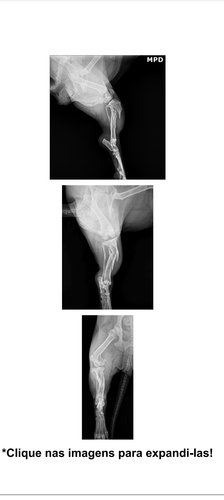

O laudo do exame radiográfico (raio-x) da Belinha é claro:

Fratura Cominutiva da Tíbia Direita: O osso da pata direita quebrou em múltiplos fragmentos, o que é muito doloroso e exige uma intervenção cirúrgica imediata para realinhar os ossos e permitir a cicatrização.

Fratura da Fíbula Direita: O osso menor da mesma pata também está fraturado.

Aumento de Volume (Edema): Há inchaço e sinais de reação inflamatória no local, indicando o sofrimento da Belinha.